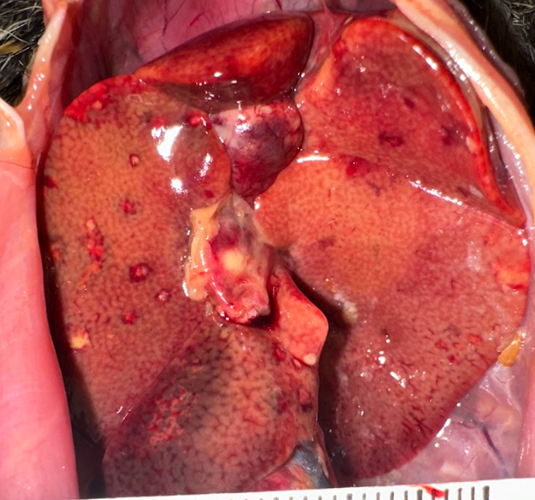

Gross Pathology:

Examined was a female marmoset in fair nutritional condition (2.5/5) with mild post-mortem autolysis. Distributed throughout all liver lobes were yellow-white and red rimmed, ~0.5 cm diameter, randomly dispersed foci that extended into the parenchyma on cut section. The parenchyma was diffusely orange with an enhanced reticular pattern (Fig. 1). The lungs were diffusely bright red and atelectatic. Sections from all pulmonary lobes floated in formalin. There was marked diffuse gas dilation of the stomach. All segments of the small intestine were moderately to markedly distended by air and contained small amounts of digesta. The pancreatic lymph node adjacent to the duodenum was approximately 3x the size of normal. The cecum and colon had multifocal white to pale tan, circular areas of serosal discoloration. There were formed feces in the colon.